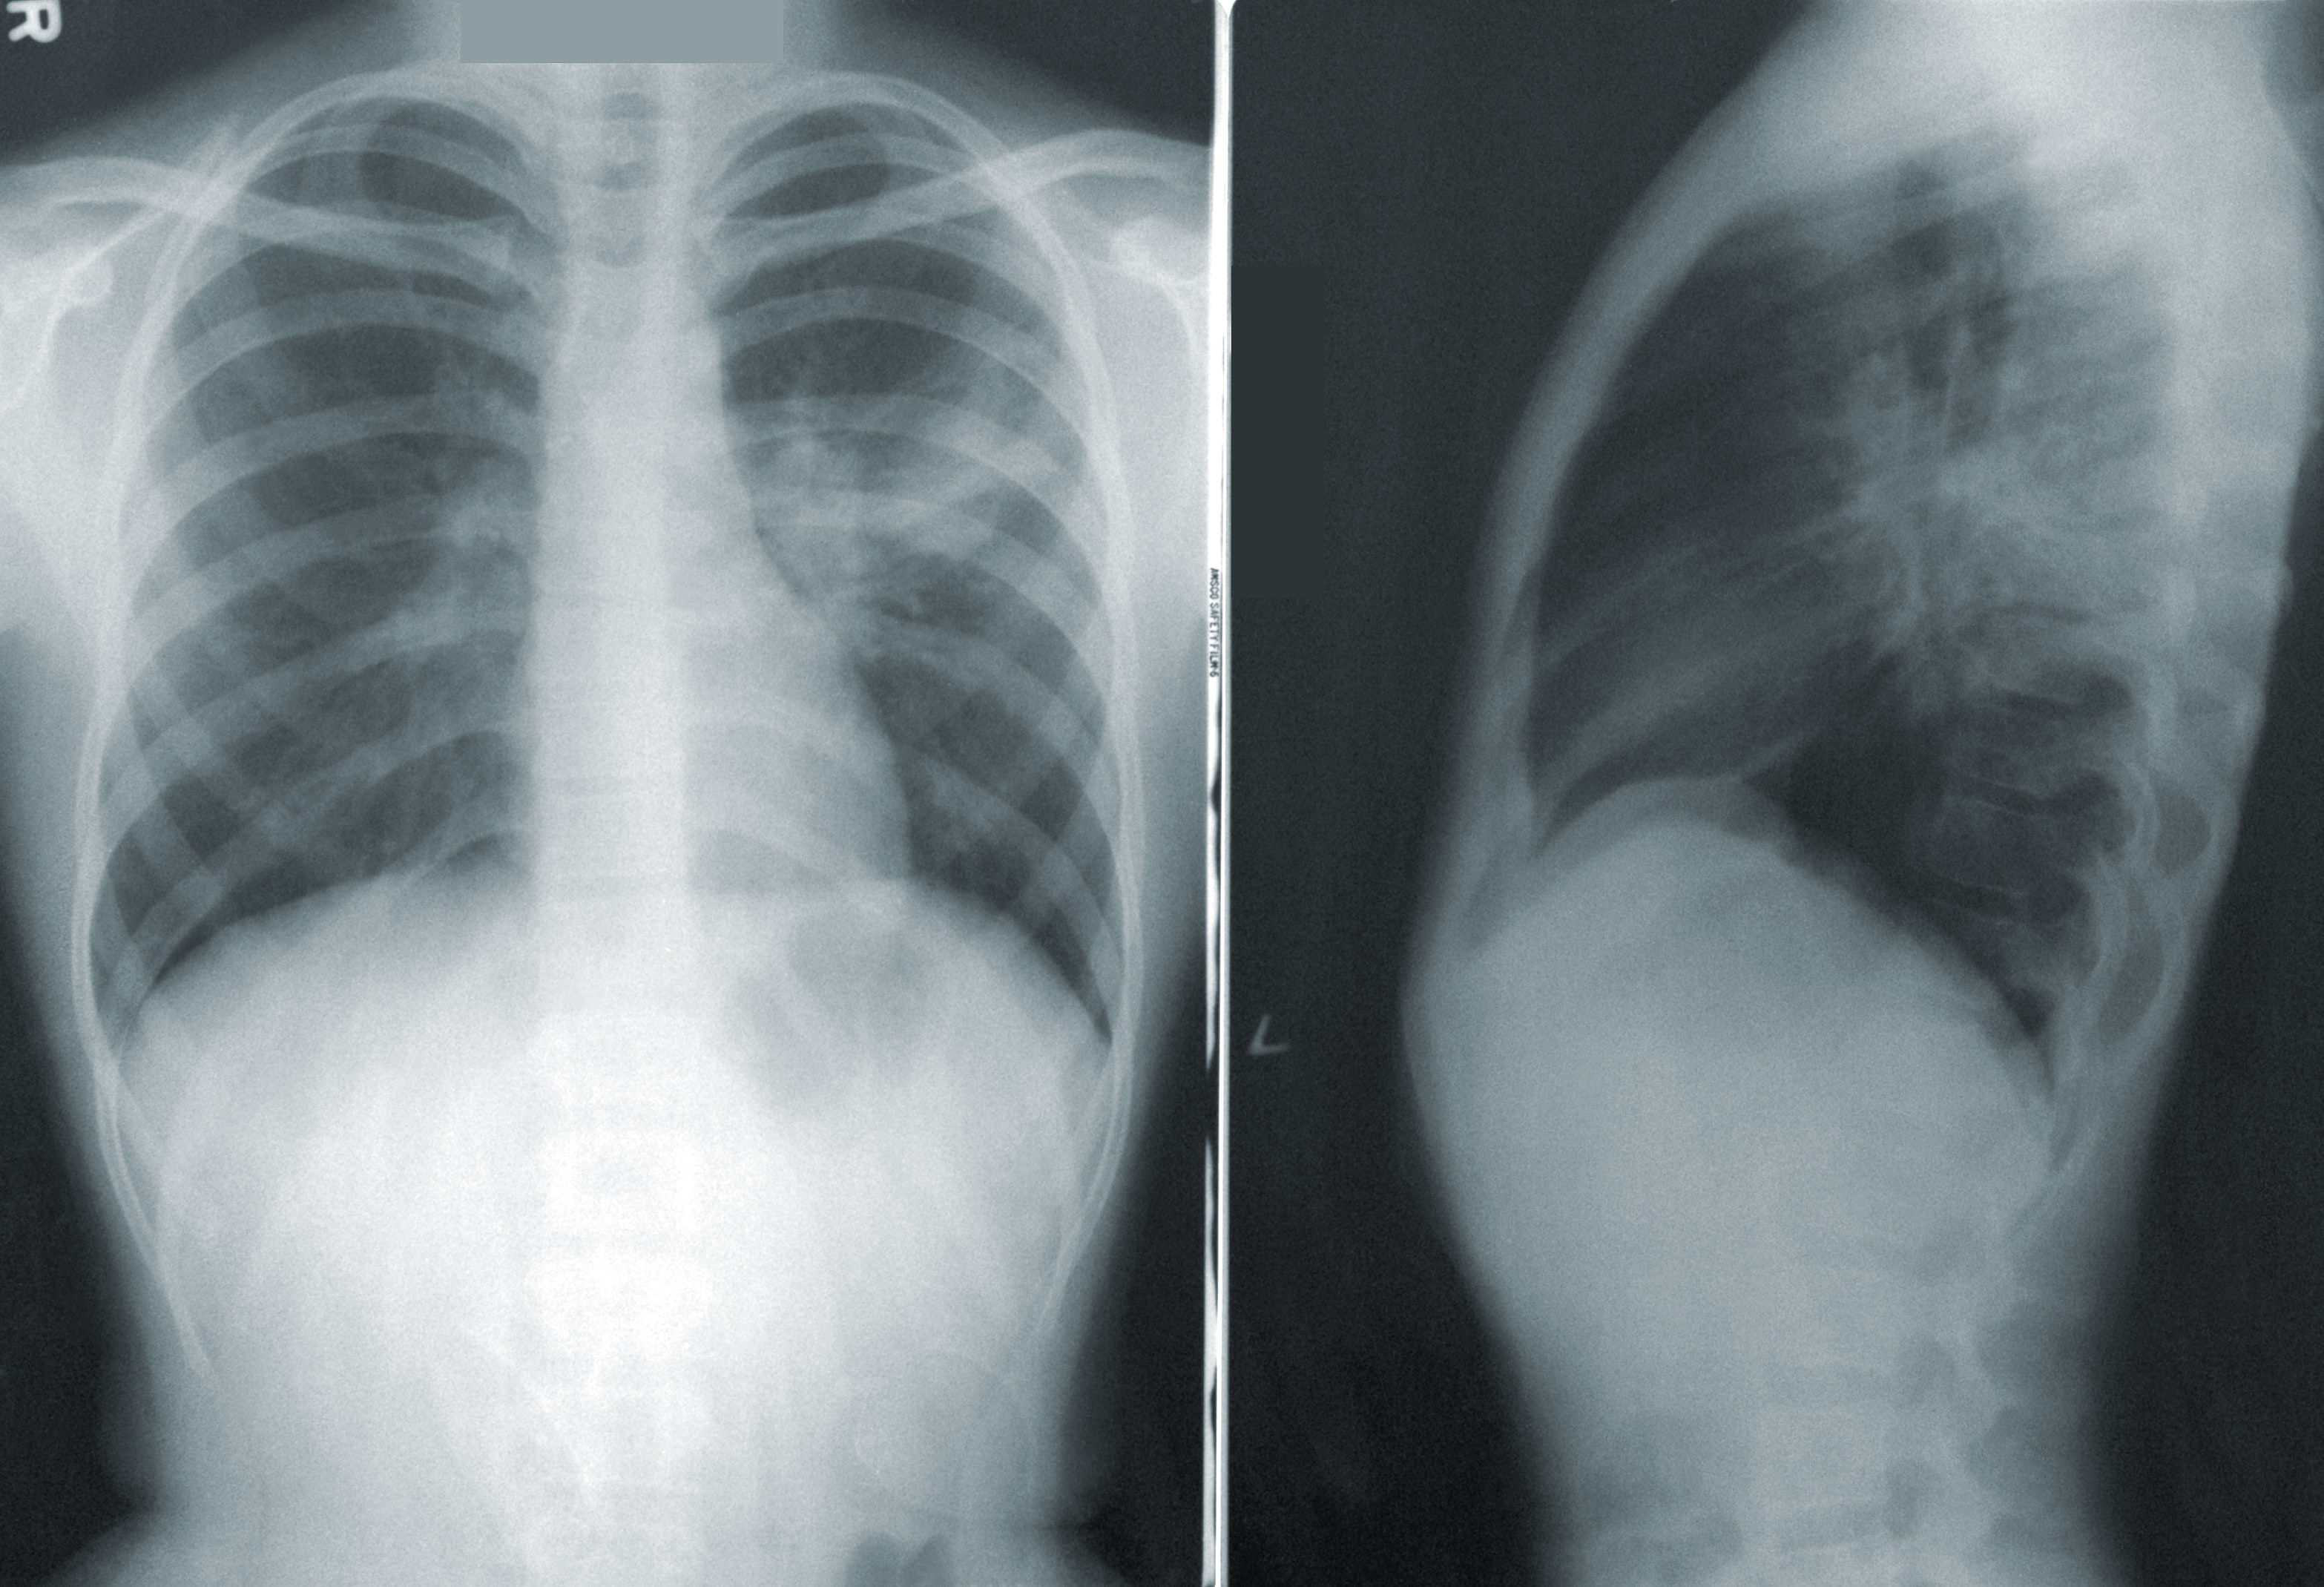

摆在医生们面前的,是一张肺部CT照片。

这张照片清晰、干净,影像轮廓与常人无二,即使是最具经验的放射科医生也会做出一致地判断:肺部健康,无异样。

但AI算法会得出不一样的结论:通过观察细微至人眼不可见的肺部斑点,它能判定这名病患已经呈现出早期肺癌的症状,应当及时治疗;如果放任不理,病情就将在未来的1~2年内,发展至能明显确诊的地步。

这套AI模型能够根据患者胸部的CT图像,诊断出早期肺癌。在去年进行的一项对比研究中,与六位经验老道的放射科医生相比,AI的准确度更高,检测到的病例增加了5%,假阳性减少了11%,AUC达到94.4%。这意味AI模型能够更早、更准确地发现癌症病例,并且显著地减少了没有患肺癌的人被误诊的几率。

此外,谷歌的该AI算法能将CT检测讯息整合为3D模型进行分析,对比传统的CT照片,3D模型不仅能够更加准确地进行医疗诊断,还能检测出传统CT检查无法清楚判断的血管异常等病症。